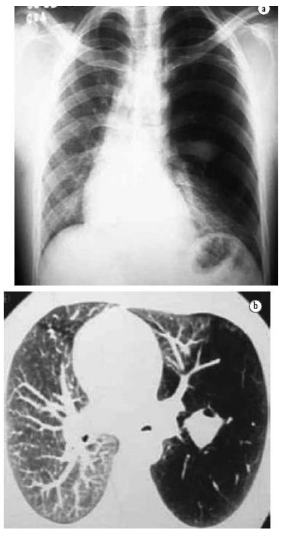

No Rx e no corte axial de TC, observa-se opacidade arredondada/tubular perihilar com parênquima adjacente hiperluzente. Identifique a combinação anatômico-radiológica compatível com o diagnóstico mostrado: